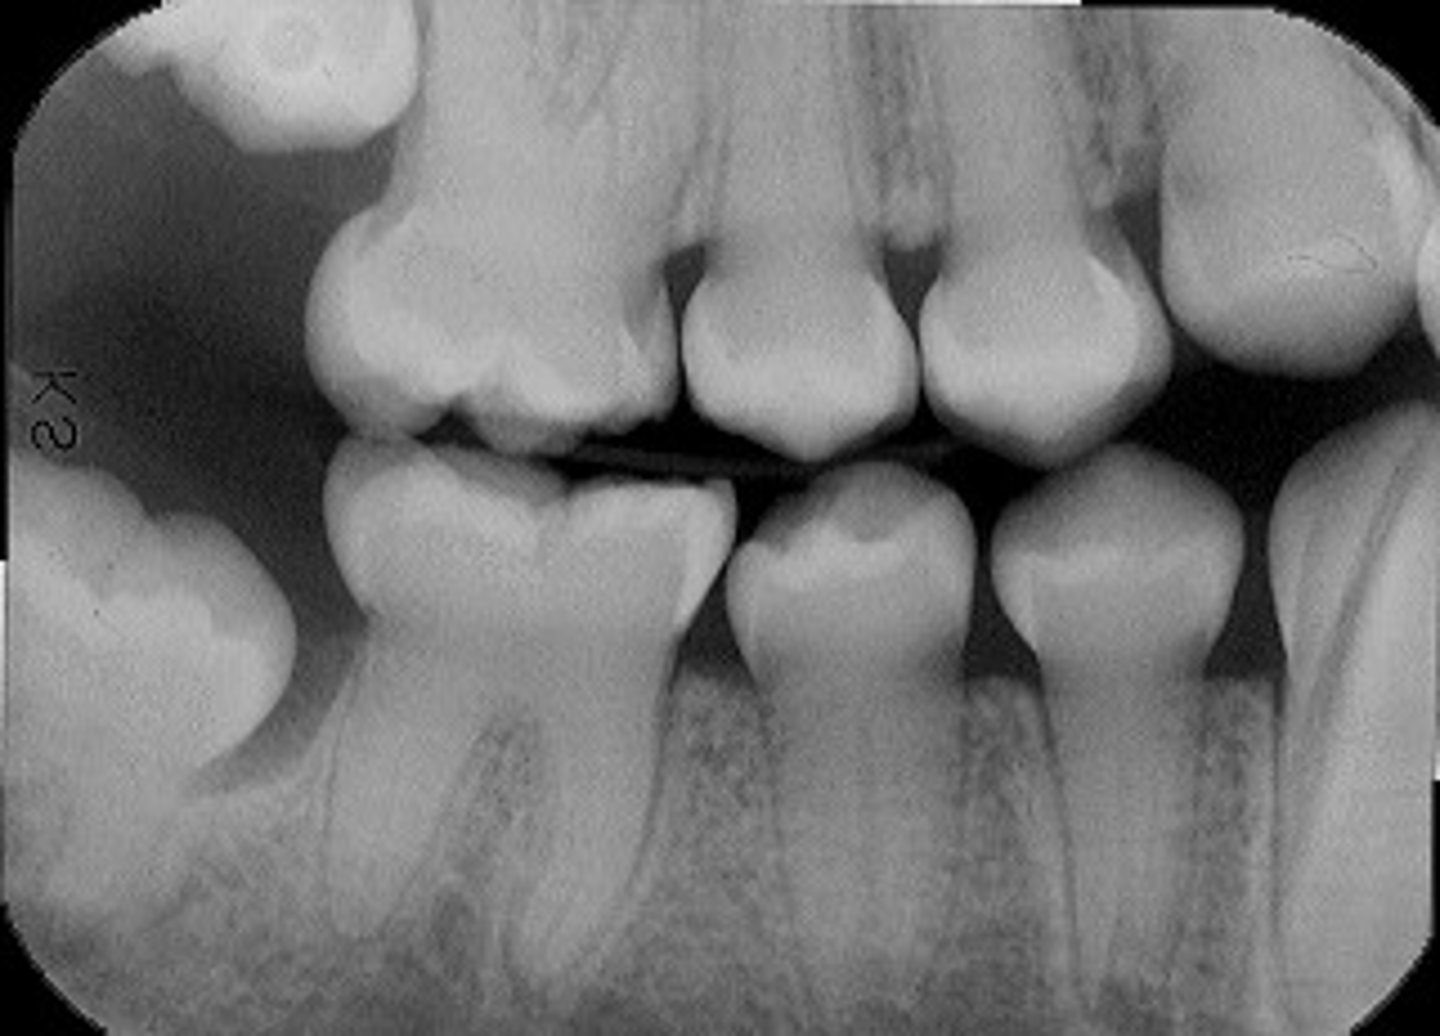

Multiple questions about eruption and looking at BW to see if its normal

STUDY ERUPTION TIMES!